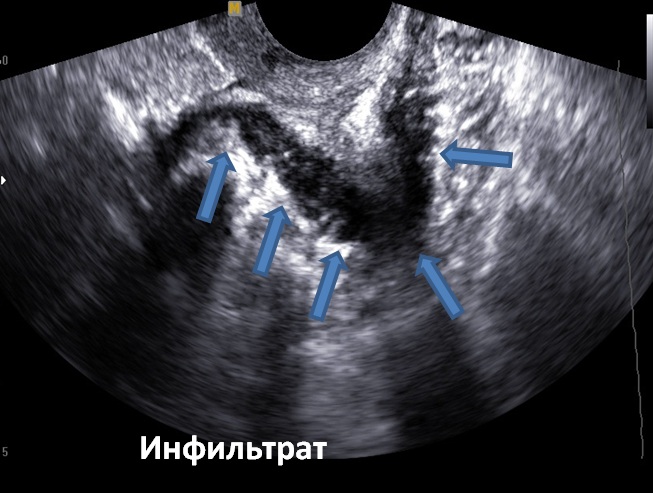

Узи покажет эндометриоз

Узи покажет эндометриоз 108 фото